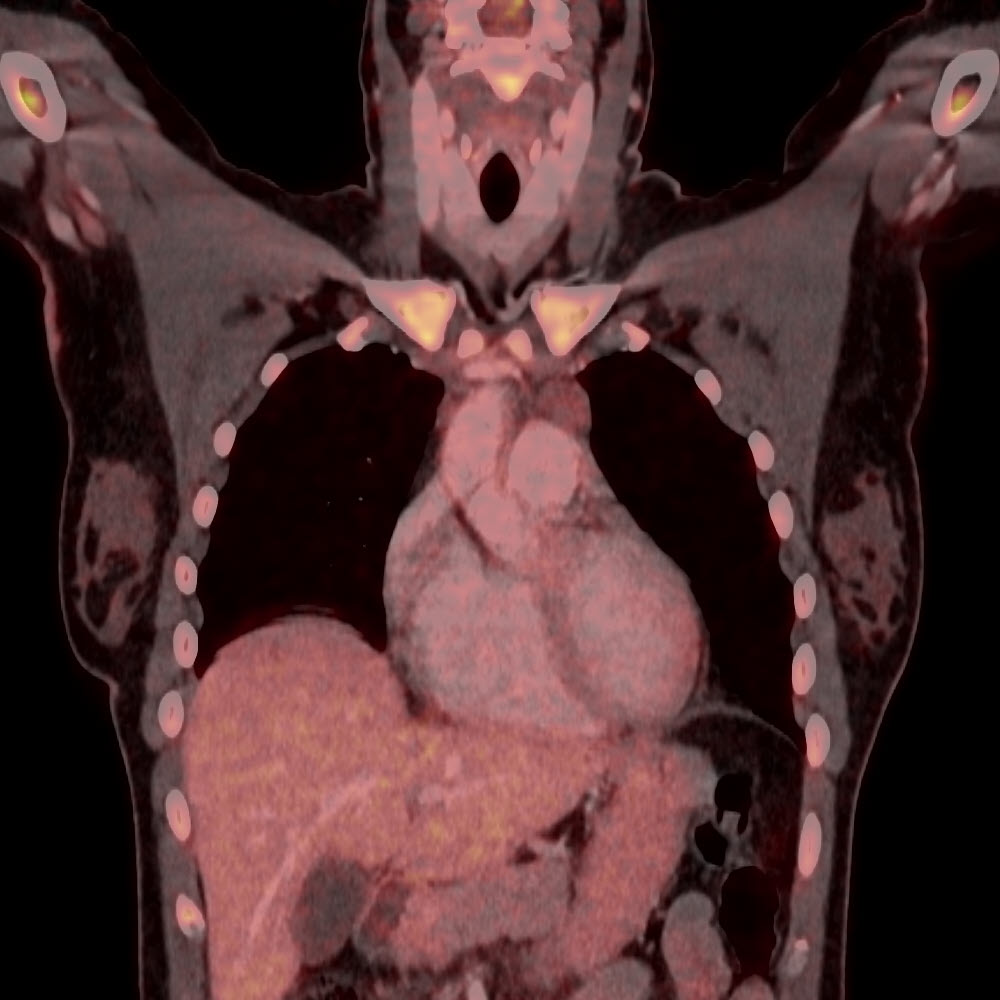

FDG-PET/CT

vor und nach Therapie

Lymphome Hals-Thorax vor Therapie

Lymphome Hals-Thorax nach Therapie